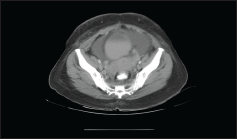

Further investigation with CT abdomen and pelvis showed moderate to gross ascites with irregular soft tissue stranding in the omentum. Bilateral irregular soft tissue density mass lesions noted in adnexa, on the right measuring 42 × 33 mm and on the left measuring 43 × 21 mm. (Figure 4). Para-aortic nodal mass seen as heterogenous conglomerate soft tissue attenuation. The stomach showed diffuse irregular wall thickening.

Figure 4. CT image showing adnexal mass.